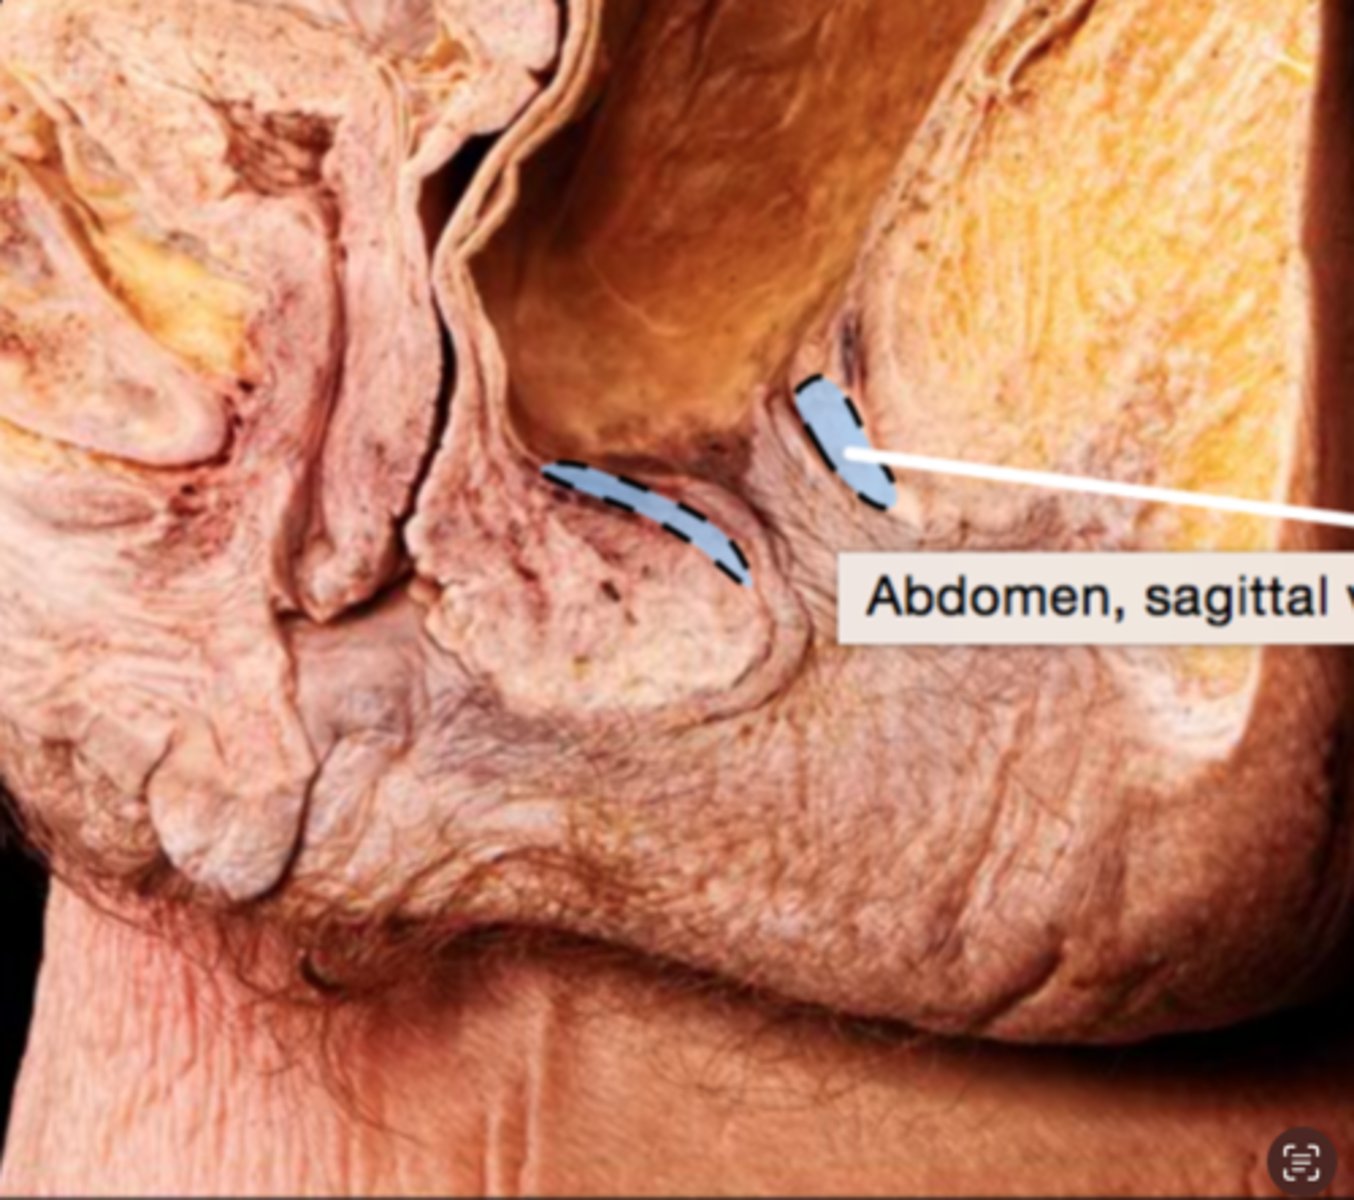

Rectum

Anal Canal

Internal Anal Sphincter

External Anal Sphincter